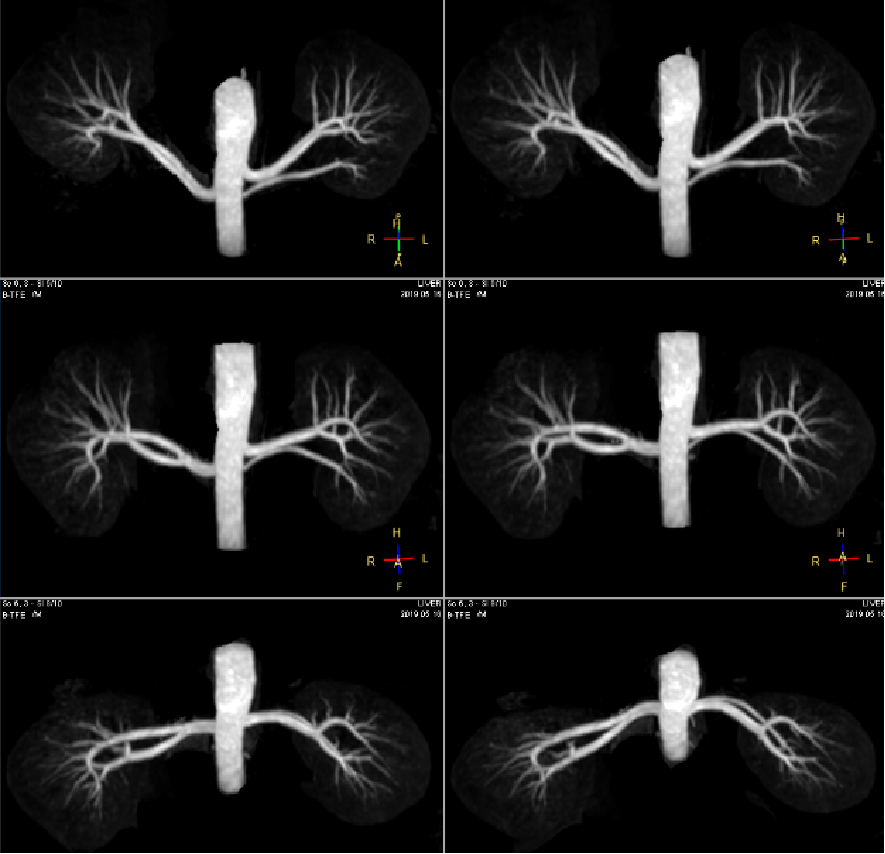

心血管系统方向

3.0T核磁依然可以做到无需造影剂全身血管成像,例如上下肢动静脉成像及颅脑动静脉成像,背景组织抑制好,有利于小血管显示。心脏扫描,可以从各方向对心脏进行扫描成像,有利于心脏疾病诊断。

肾血管